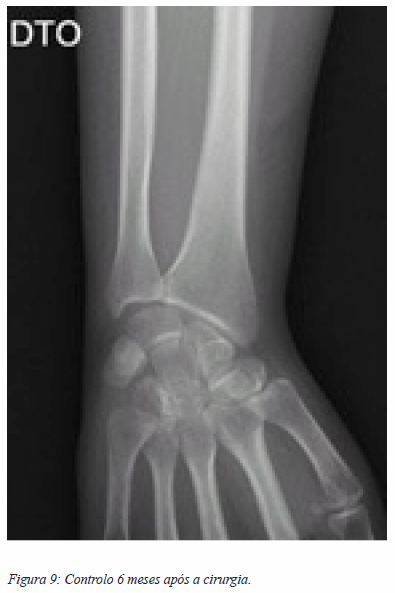

No dia 12 Março 2015 é submetida a exérese em bloco do tumor ósseo recidivado do unciforme direito e preenchimento do espaço com hemitendão do grande palmar (figuras 7, 8 e 9). Optámos pelo hemitendão do grande palmar porque intra-operatoriamente verificámos que a doente tinha uma variante anatómica do normal e não apresentava o músculo pequeno palmar que seria, em condições normais, a nossa primeira opção para fazer a almofada biológica.

O exame anatomo-patológico apresentava células gigantes multinucleadas, tipo osteoclasto e células mononucleadas, com ligeiro pleomorfismo e raras mitoses (figura 10 e 11), aspetos que apontam para um tumor de células gigantes do osso. Seis meses após a cirurgia, a doente não apresenta sinais de recidiva da doença, e mantém a amplitude de todos os movimentos do punho, não tendo sido medida objetivamente a força de preensão.

Neste momento, temos 6 meses de seguimento da doente, e esta não apresenta qualquer sinal de recidiva local da lesão, sendo que clinicamente a doente apresenta força e mobilidade do punho e mão normais.